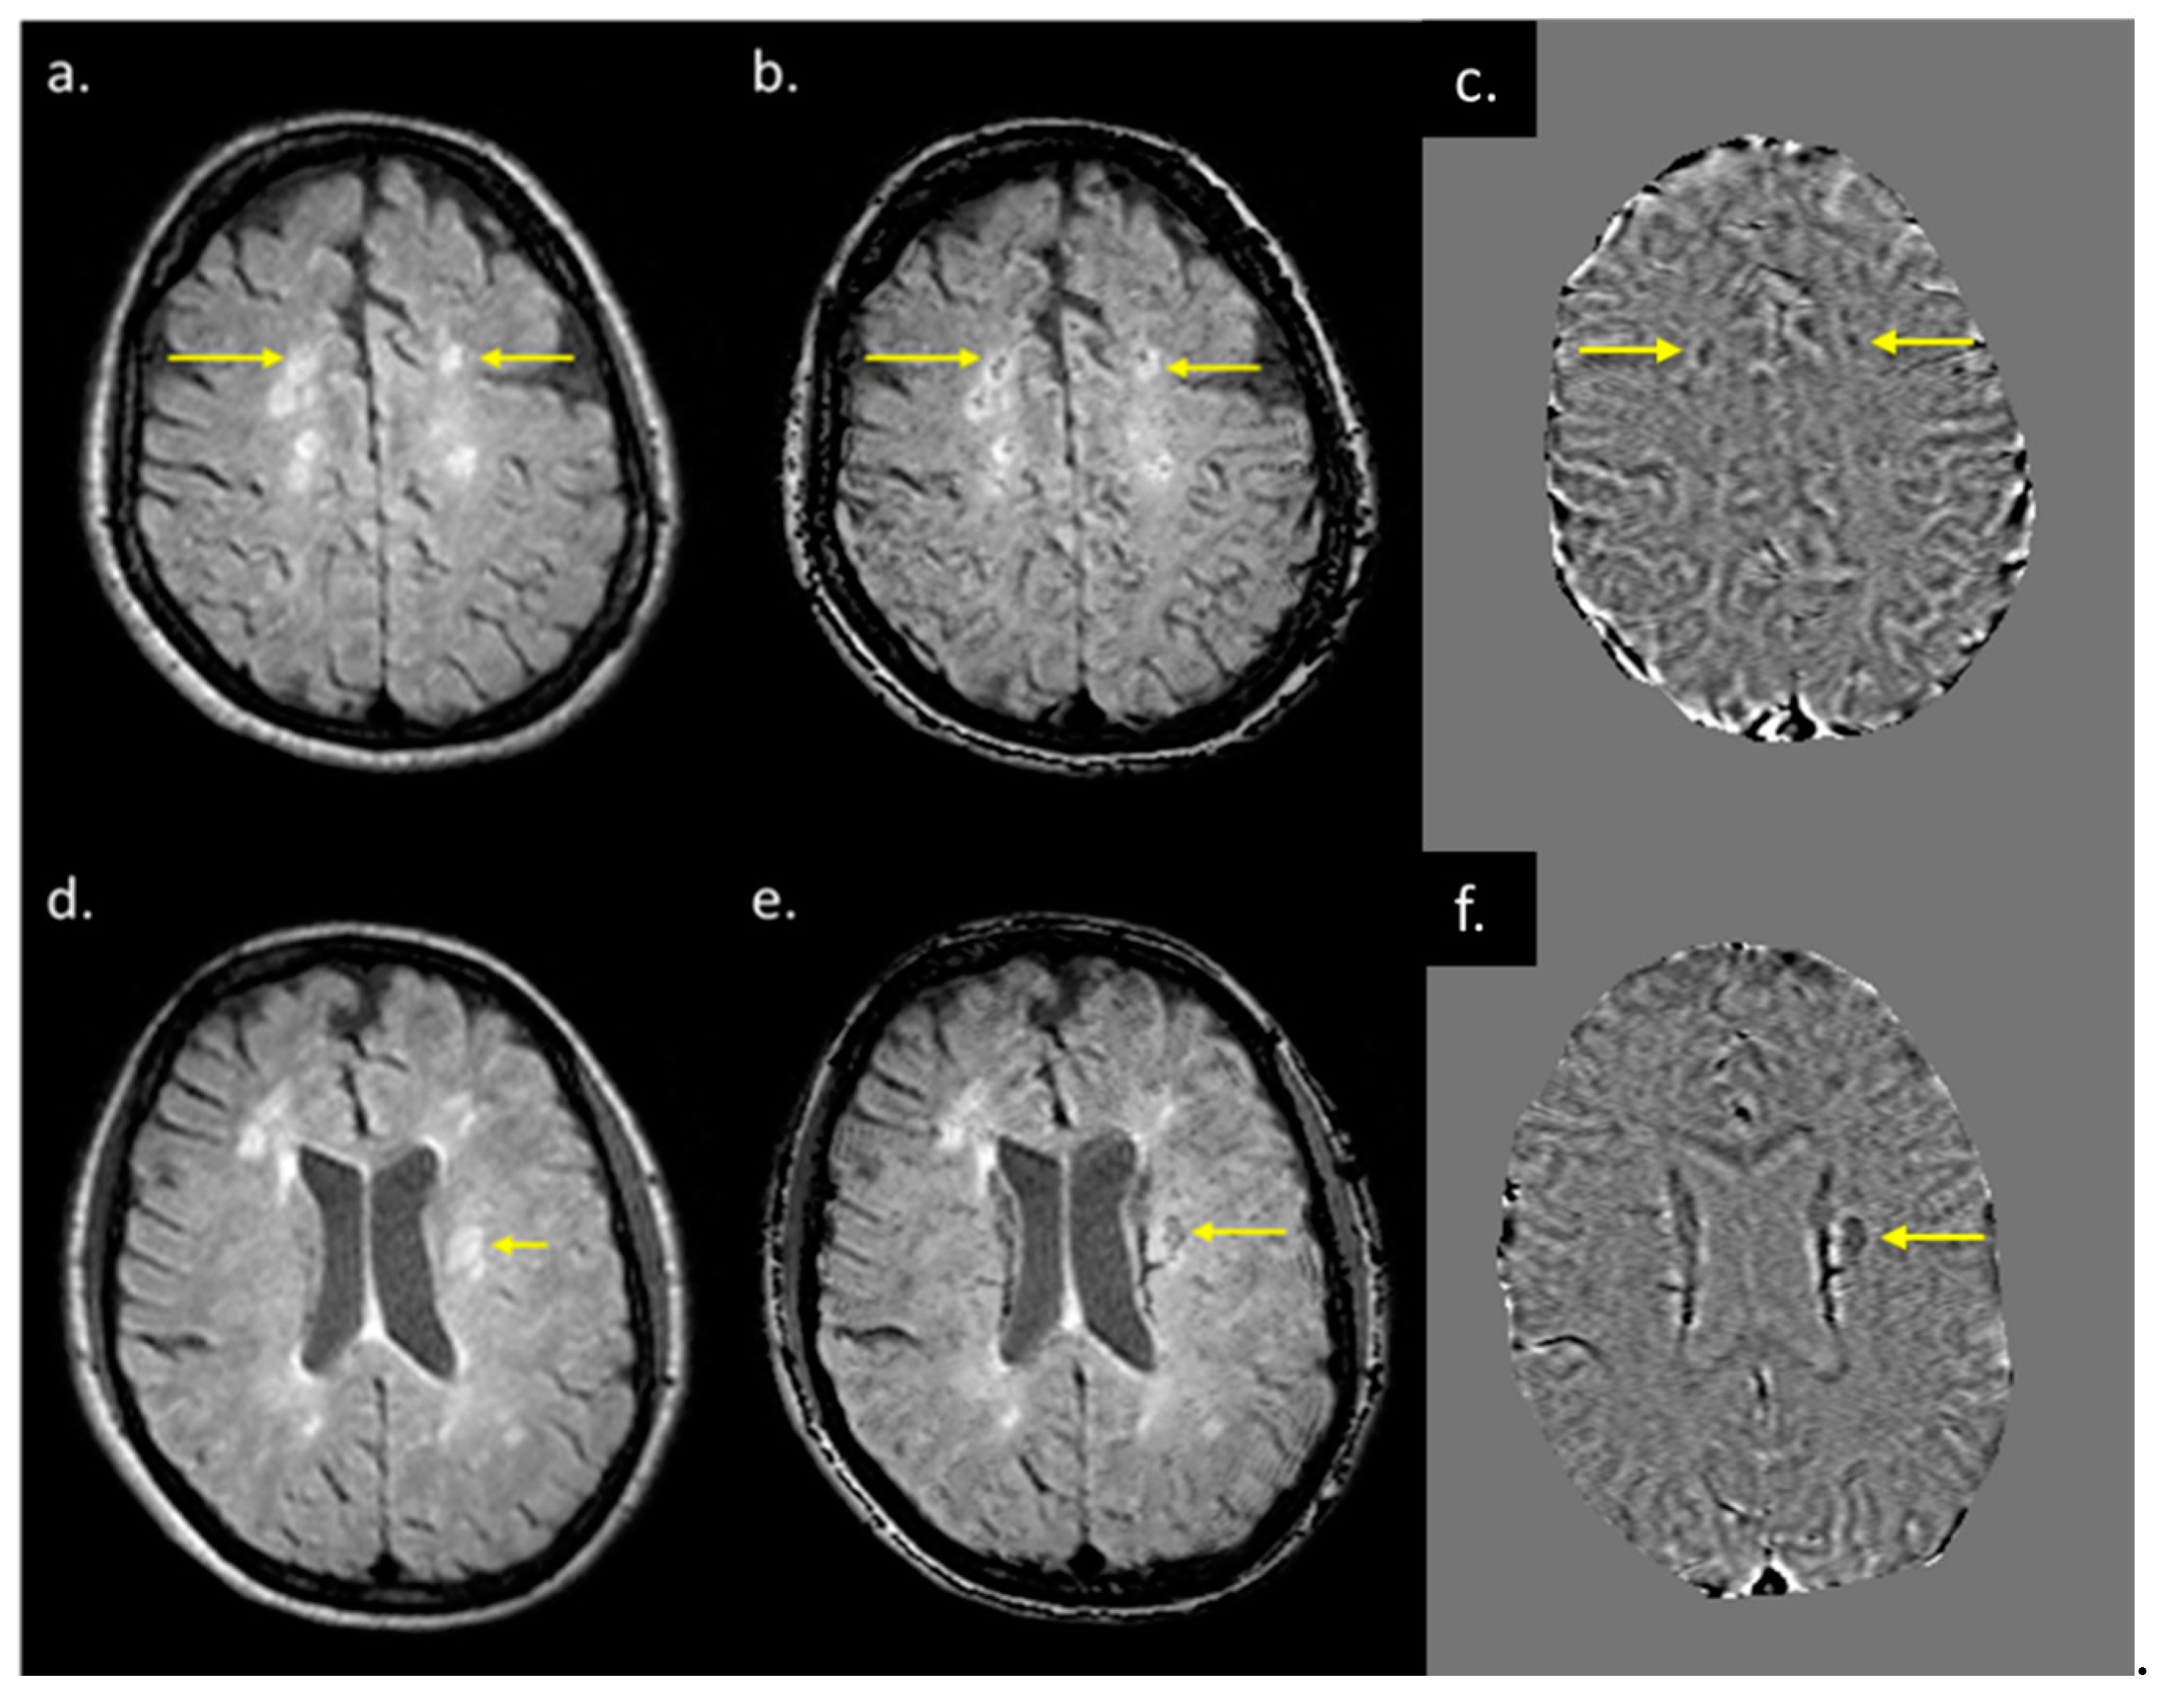

The lesions and the NAWM regions showed a clear separation in signal and/or tissue properties for all sequences. For MS lesions that appeared clearly in QSM relative to NAWM, their intensities showed a strong separation between MTR, T2WI, FA and ADC (see Figure 4). The DTI measures, including FA, ADC and RD are plotted against each other in Figure 5 and showed a strong correlation with one another. The SWI-FLAIR images were used to show which lesions had a significant positive susceptibility change (increased paramagnetism) of the WM, potentially signifying demyelination (Figure 6). Typically, the T2 FLAIR lesions extended beyond the boundary of the QSM or SWI-phase visible lesions.

Figure 6.

T2 FLAIR images (a,d), fusion image of susceptibility weighted imaging (SWI) phase and T2 FLAIR (b,e), and SWI phase (c,f) from two patients both with QSM and T2 FLAIR visible lesions. When T2 FLAIR images (a,d) have an SWI phase mask superimposed on them (c,f), possible regions of demyelination (shown by yellow arrows in (b,e) can be differentiated from those showing inflammation alone (b,e).